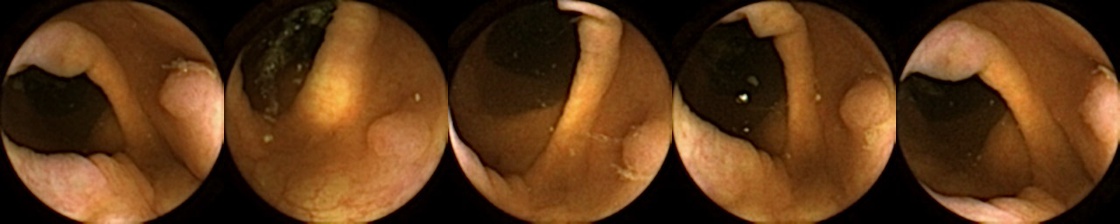

Figure 3 shows classification output examples for the MIV model using the pretrained ConvNext. Note that the model has a test accuracy of 83.66% for DBA L2 with 2 heads. In each row, the leftmost image is the query and the four images to the right of each query are the target images. The True Positive (left-top) and True Negative (bottom-right) examples outline the cases when the model is able to successfully distinguishes images containing unique polyps from those with dissimilar polyps. The False Negative (top-right) and False Positive (bottom-left) examples show the cases where the model fails to correctly distinguish images of unique polyps and images of dissimilar polyps. Further, we can note from the differences in the examples of True Positives and False Negatives that when the query image and the target set instances differ from each other in some ways, then the model can misclassify images. These differences could be attributed to different views due to the dynamics of the camera inside the colon, different views from two camera heads of the capsule, or presence of artifacts such as bubbles, debris, and small bowel secretions.

We can additionally consider the confusion matrices from the best MIV model associated with (a) the pretrained ConvNext and (b) SimCLR pretraining using the ConvNext backbone in Figure 5. We note that using SimCLR achieves a better ratio of False Negatives (70) to False Positives (38) as compared to pretrained ConvNext, which has 109 False Negatives and 23 False Positives.